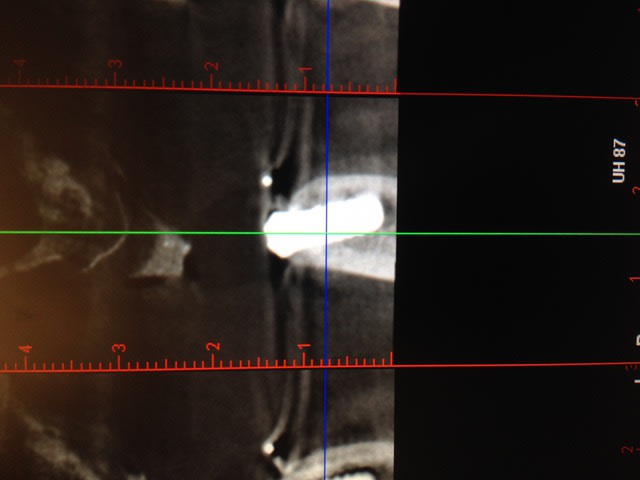

implant Straumann Tissu level posé il y a 6 mois

En dehors de la corticale non car j'avais fait un scan de contrôle il y a 3 mois. De plus on était dans un cas d'extraction implantation donc dans la racine que j'ai extraite.

scan

J'ai revu le scan de départ. Pour cet implant, il ne s'agissait pas d'une extraction implantation. Forage classique. Je suis toujours dans le désarroi.